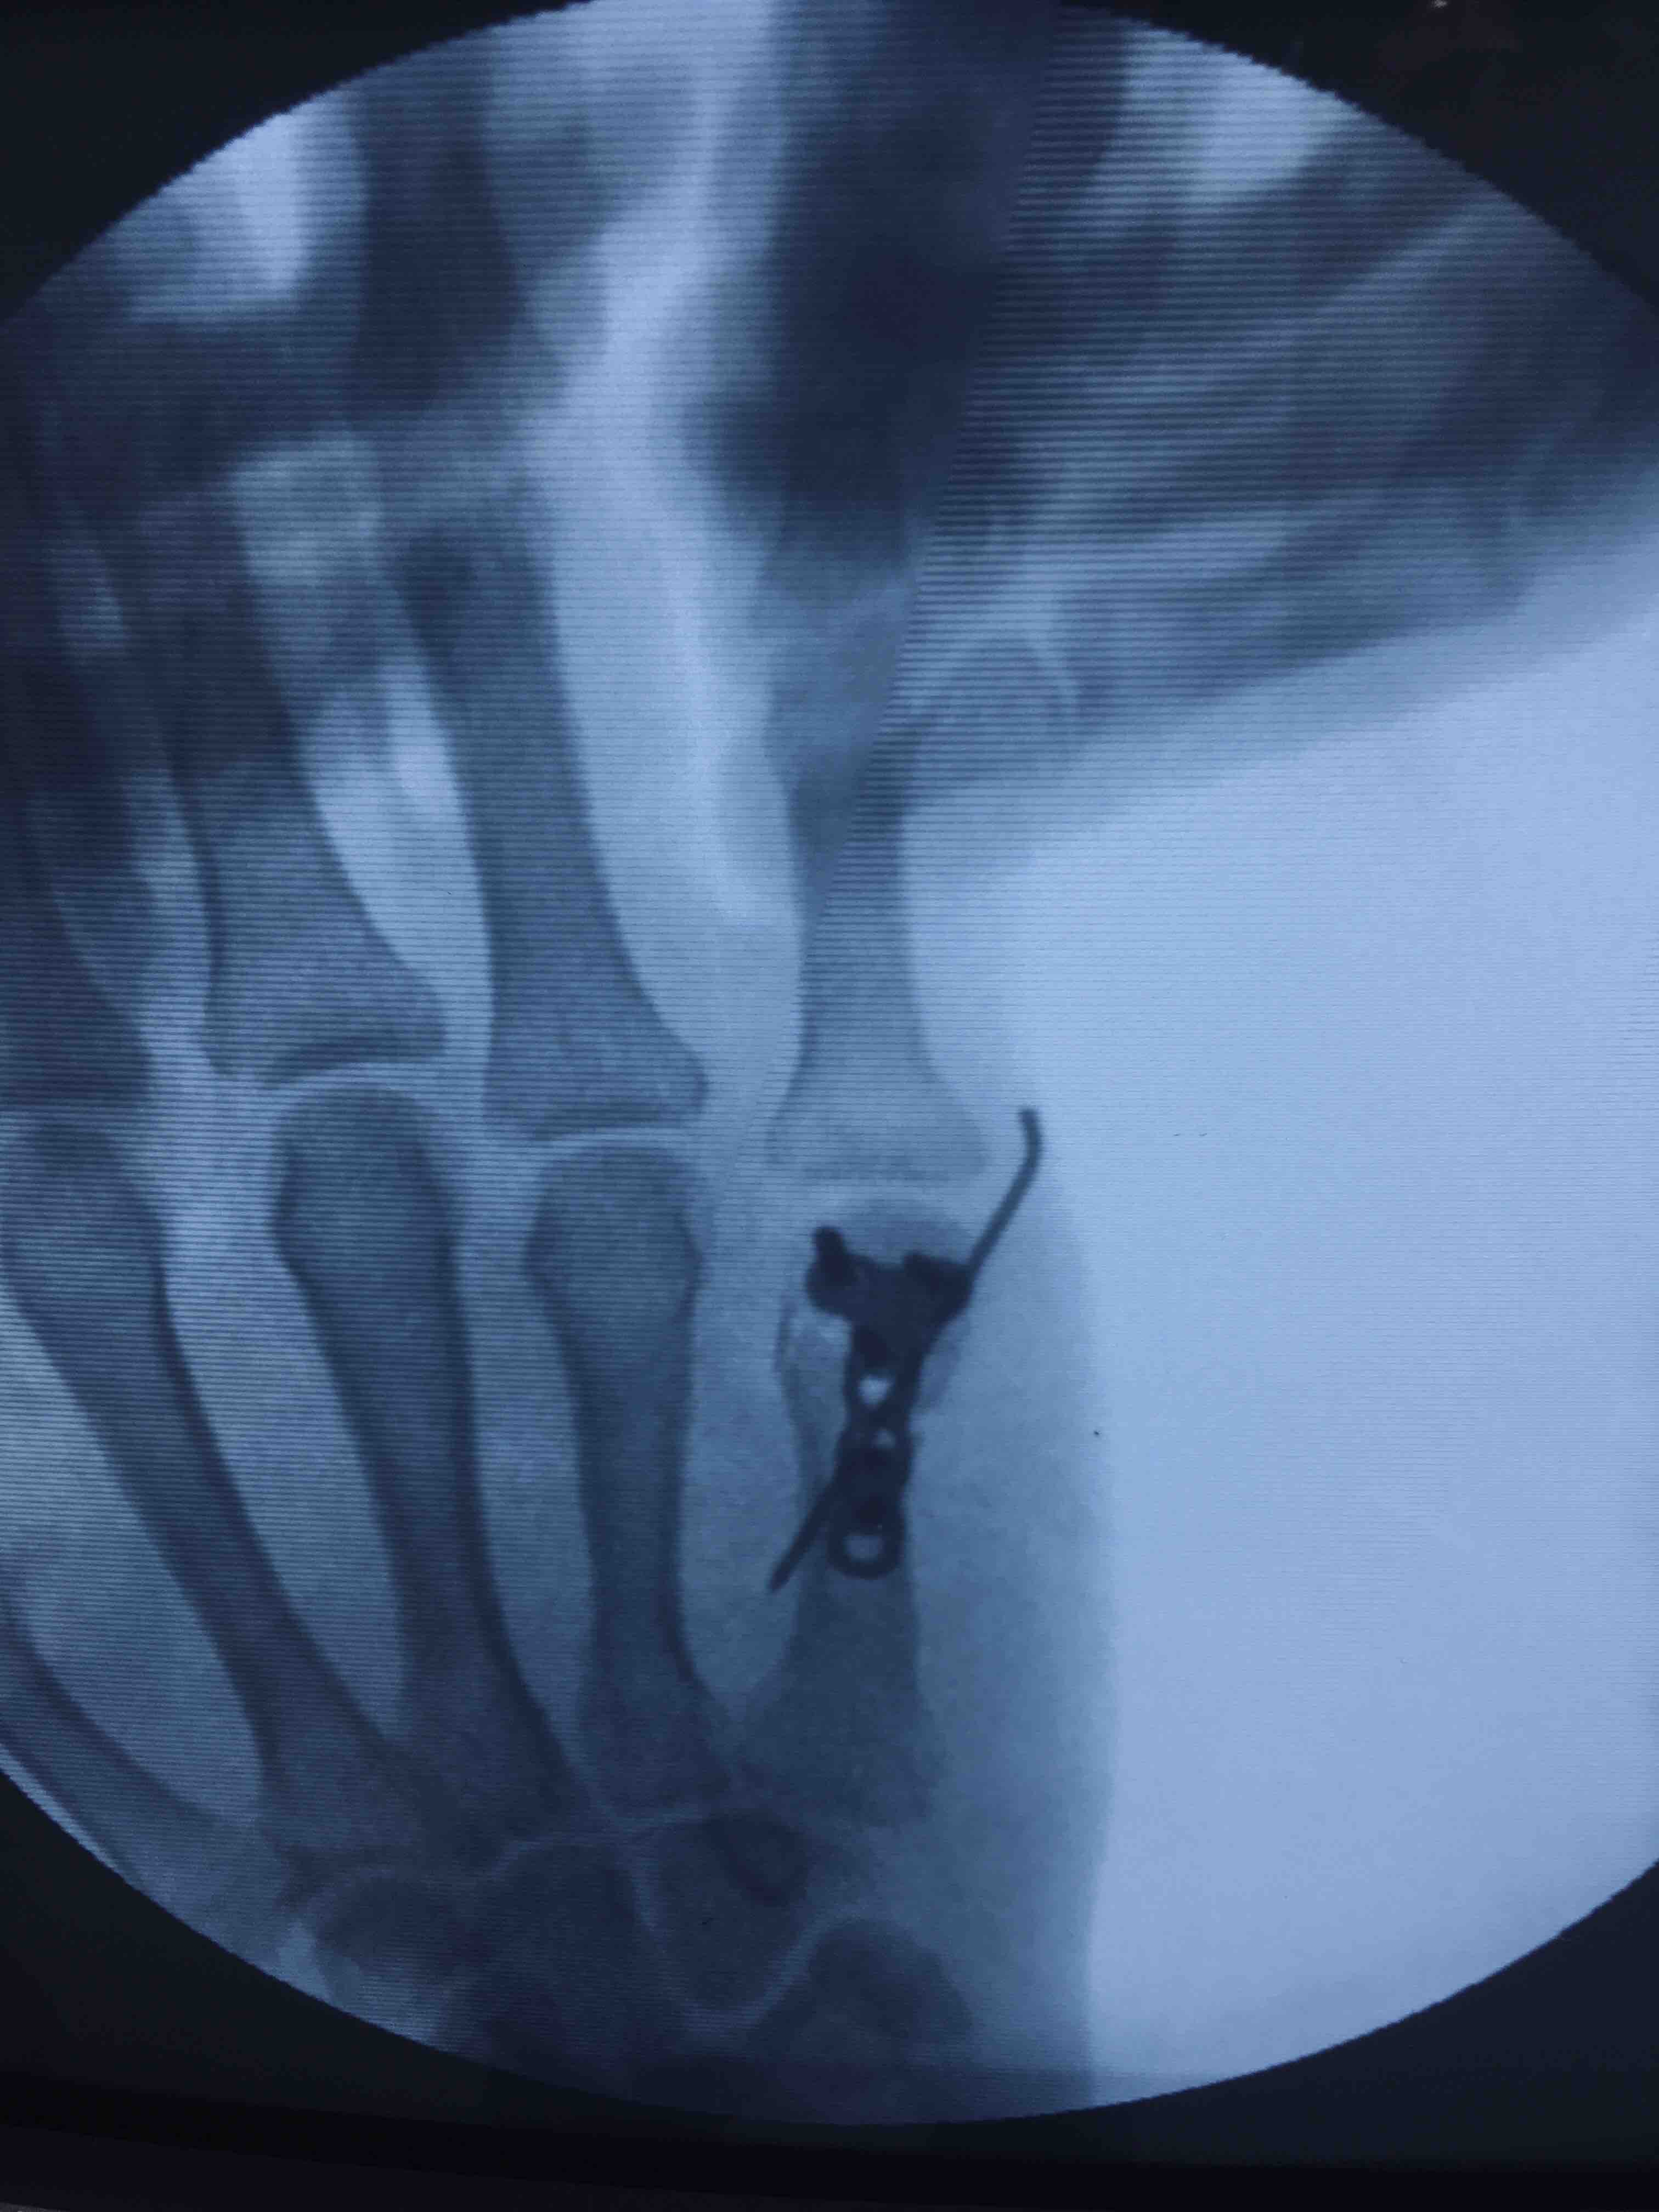

掌骨头粉碎性骨折(切复内固定术)

摔伤后右手疼痛1小时入院。既往因右手第五掌骨头骨折行闭合复位固定术。

右手第五掌指关节处肿胀,局部皮色皮温正常,压痛及纵向叩击痛阳性,末梢血运感觉正常,掌指关节活动受限。

臂丛麻醉下行切复内固定术,术后制动